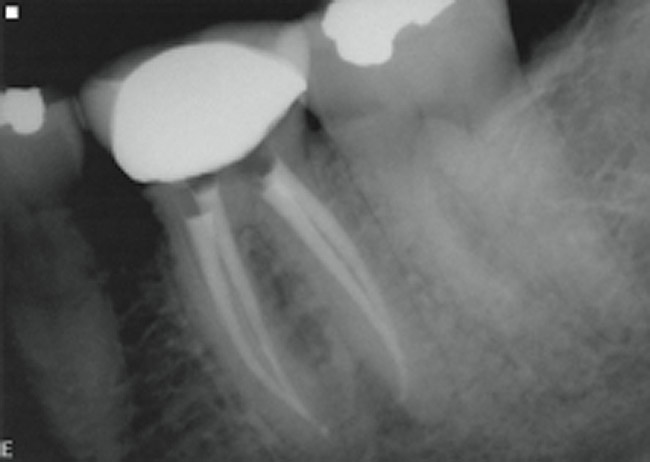

Figure 2  Access was made through the crown and the post in the distolingual canal was isolated conservatively and removed along with the root canal filling material.

Figure 2

Figure 3  One-month postoperative radiograph. The patient’s symptoms have disappeared completely in the area. The access opening will now be filled definitively.

Figure 3

A 40-year-old man presented with a chief complaint of occasional chewing discomfort in a tooth with a history of endodontic therapy (Figure 1). The patient recounted a 1-hour visit with his dentist for the root canal therapy and subsequent visits to fabricate the crown. Eight months after the initial root canal therapy and coronal restoration, mild chewing discomfort persisted in the tooth. After discussing options and giving consent, a nonsurgical re-treatment through the new crown with intracoronal removal of the post was performed to address the patient’s chief complaint while attempting to retain the new crown (Figure 2). A 1-hour appointment was necessary to achieve these objectives (Figure 3). The patient’s symptoms disappeared and the access preparation was subsequently restored.

This case best explicates the word efficiency as it pertains to clinical endodontics. While the original root canal and the re-treatment were both performed within the same time frame, the quality, the standard of care, and, inevitably, the outcome were dissimilar in the same tooth. The first procedure was performed quickly; the second was done efficiently. This brings up the question of skill and experience as functions of efficiency in clinical procedures.